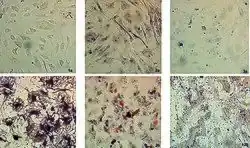

Authors: Vitalii Moskalov, Olena Koshova, Sabina Ali, Nataliia Filimonova

Objective. To determine such parameters of humoral immunity as the number of antibody-forming cells and the titer of antibodies in the blood under the action of the whole fraction of the secretome of xenogenic mesenchymal stem cells in mice with a normal immune status and mice with secondary immunodeficiency caused by the hydrocortisone acetate. [...] Methods. The following methods were used in the study: isolation of mesenchymal stem cells from the bone marrow of cattle; culturing of isolated cells and obtaining a conditioned medium containing exometabolites with subsequent purification; modeling of secondary immunodeficiency in mice; setting up a test on mice to determine the number of antibody-forming cells in the spleen and hemagglutinin titers in blood serum; statistical data analysis. Results. A study of the impact of the secretome of xenogenic mesenchymal stem cells (MSCs) on the humoral arm of immunity in mice with a normal immune status showed a significant increase in the antibody-forming cells count compared with the control by 3.4-8.8 times when administered intramuscularly and by 4.2-5.4 times when administered subcutaneously (at the same time, in the group of the reference drug, the increase was four times), as well as an increase in the titer of hemagglutinins concerning the control by 25-95% when administered intramuscularly and 32-52% when administered subcutaneously (the reference drug Thymalin was at the control level). With intramuscular administration, a clear relationship was observed between the concentration of MSC secretome and the biological effect (high significant positive correlation: ρ = 0.99, p ≤ 0.05 for calculating AFC; ρ = 0.97, p ≤ 0.05 for HA titer). Lethality in the group of animals what administered only hydrocortisone acetate (HCA, positive control) was 100%. The use of the mesenchymal stem cells secretome increased the survival of animals by 50% by stimulating the formation of the required number of antibody-forming cells and antibody titer, except for the subcutaneous route of administration (at the level of immunized control, animals with a normal immune status). The reference drug showed a result at a level significantly lower than the immunized control. The antibody titer with the subcutaneous route of administration of secretion of MSCs was significantly lower than the immunized control but significantly higher concerning the reference drug. Conclusion. The administration of the secretome of xenogenic mesenchymal stem cells stimulated the humoral arm of immunity as same in mice with normal immune status as in mice with secondary immunodeficiency. The data obtained supplement the information on the introduction of live mesenchymal stem cells. Live allogeneic MSCs have a suppressive effect on B cells, while xenogenic MSCs cause a response on themselves. The secretome of xenogenic MSCs does not contain surface immunogenic molecules that are carried by living cells, but nevertheless increases the activity of the humoral component of immunity. The mechanisms of this effect require further study. doi: 10.15347/WJM/2023.004